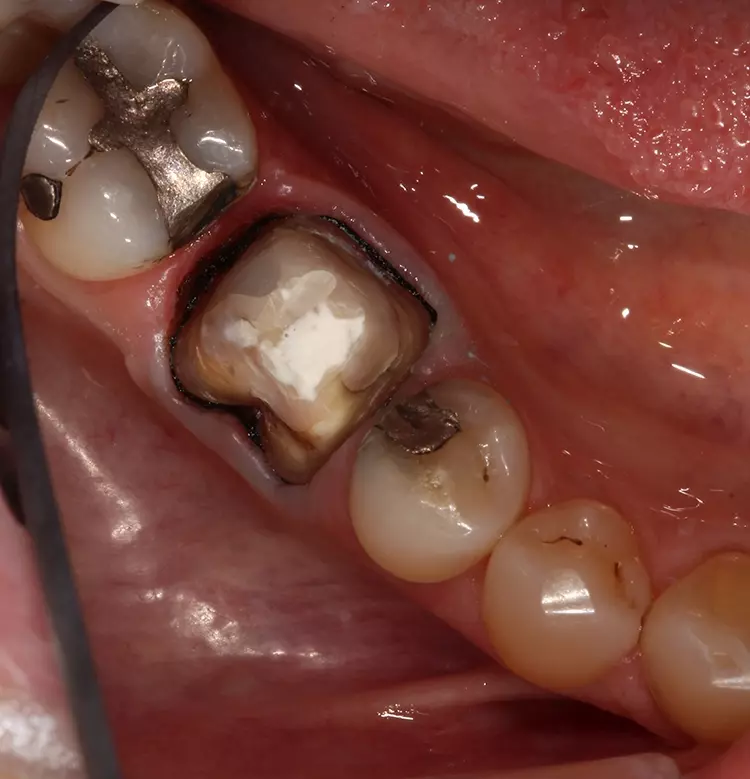

Die Präparation für die neue Krone erfolgte mit konischen Fräsern grober und mittlerer Körnung (850.014C/M, Solo Diamond). Nach der Kariesentfernung war eine Anhebung der tief liegenden Kavitätenränder erforderlich, die ebenso wie auch der Aufbau des restlichen Stumpfes mit VisCalor bulk (VOCO) erfolgte. Um eine Weichgewebskonditionierung zu ermöglichen, wurde eine provisorische Krone hergestellt, die der Patient vor der digitalen Abformung einige Wochen getragen hat (Abb. 2a und 2b).

Die provisorische Krone wurde mit Komposit auf der distalen Seite verstärkt. Zur morphologischen Adaptation des Weichgewebes trug der Patient die provisorische Krone für einige Wochen. So konnten gleichzeitig die Bedingungen für eine präzise Abformung geschaffen werden.

Die provisorische Krone wirkt etwas unförmig (Abb. 2), was auf die mangelnde Ästhetik der ursprünglichen Krone zurückzuführen ist. VOCO Retraction Paste ist ein pastöses Produkt, das in einem Cap zur direkten Anwendung erhältlich ist. Es hat ausgezeichnete adstringierende Eigenschaften und hinterlässt, wie in diesem Fall zu sehen ist, einen trockenen und gut geweiteten trockenen Sulkus – ideale Voraussetzungen für eine hochpräzise Abformung.